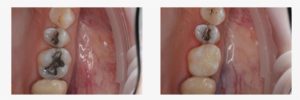

• 100% náhrada zuboviny ideální pro výplně I. a II. třídy

• vysoká pevnost v ohybu >100 MPa zajišťuje odolnost a dlouhou životnost

• JEDEN odstín s translucencí 11% pro přirozený vzhled